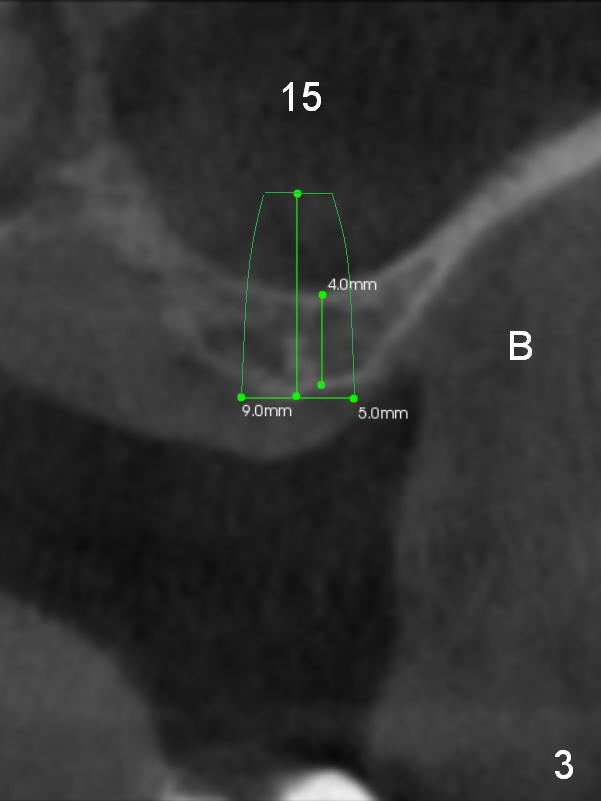

Although the patient agrees to have the tooth #13 with mobility II removed, implants at #14 and 15 should help alleviate occlusal trauma to the former. Initial osteotomy depth will be 1 and 2 mm at #14 and 15 (Fig.1: 1-2 mm from the sinus floor), followed Magic Sinus Lifter and bone graft. Implants to be placed are going to be 5x9 (at #15) or 5x7 (at #14) mm (Fig.2,3). Abutments (6x4(2) mm) will be placed if primary stability is achieved. Prepare torque wrench and the adaptor to measure torque value. Immediate splinted provisional is to be fabricated with occlusal reduction at #13.